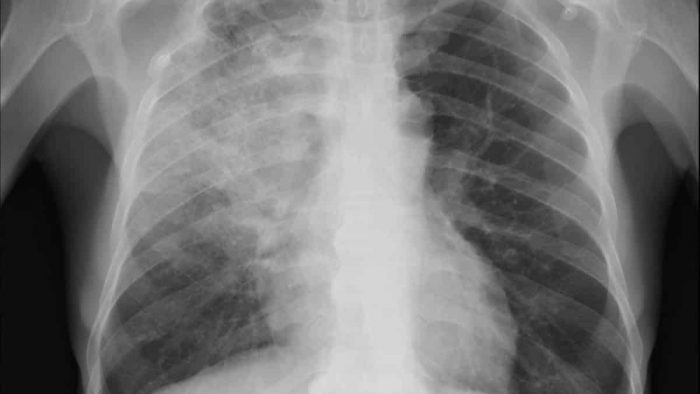

Outro fator que chamou a atenção dos pesquisadores foi a confirmação do aumento na densidade do pulmão, que fica com “o aspecto de branco jateado, chamado na medicina de ‘vidro fosco’ ”. Essa é uma característica muito forte dos pacientes com a covid-19, como já relatado em vários artigos científicos. “Na covid-19 o ‘vidro fosco’ tem apresentado uma forma diferente até em relação a outras patologias que apresentam essa característica, por isso o aplicativo consegue agrupar”, comenta.